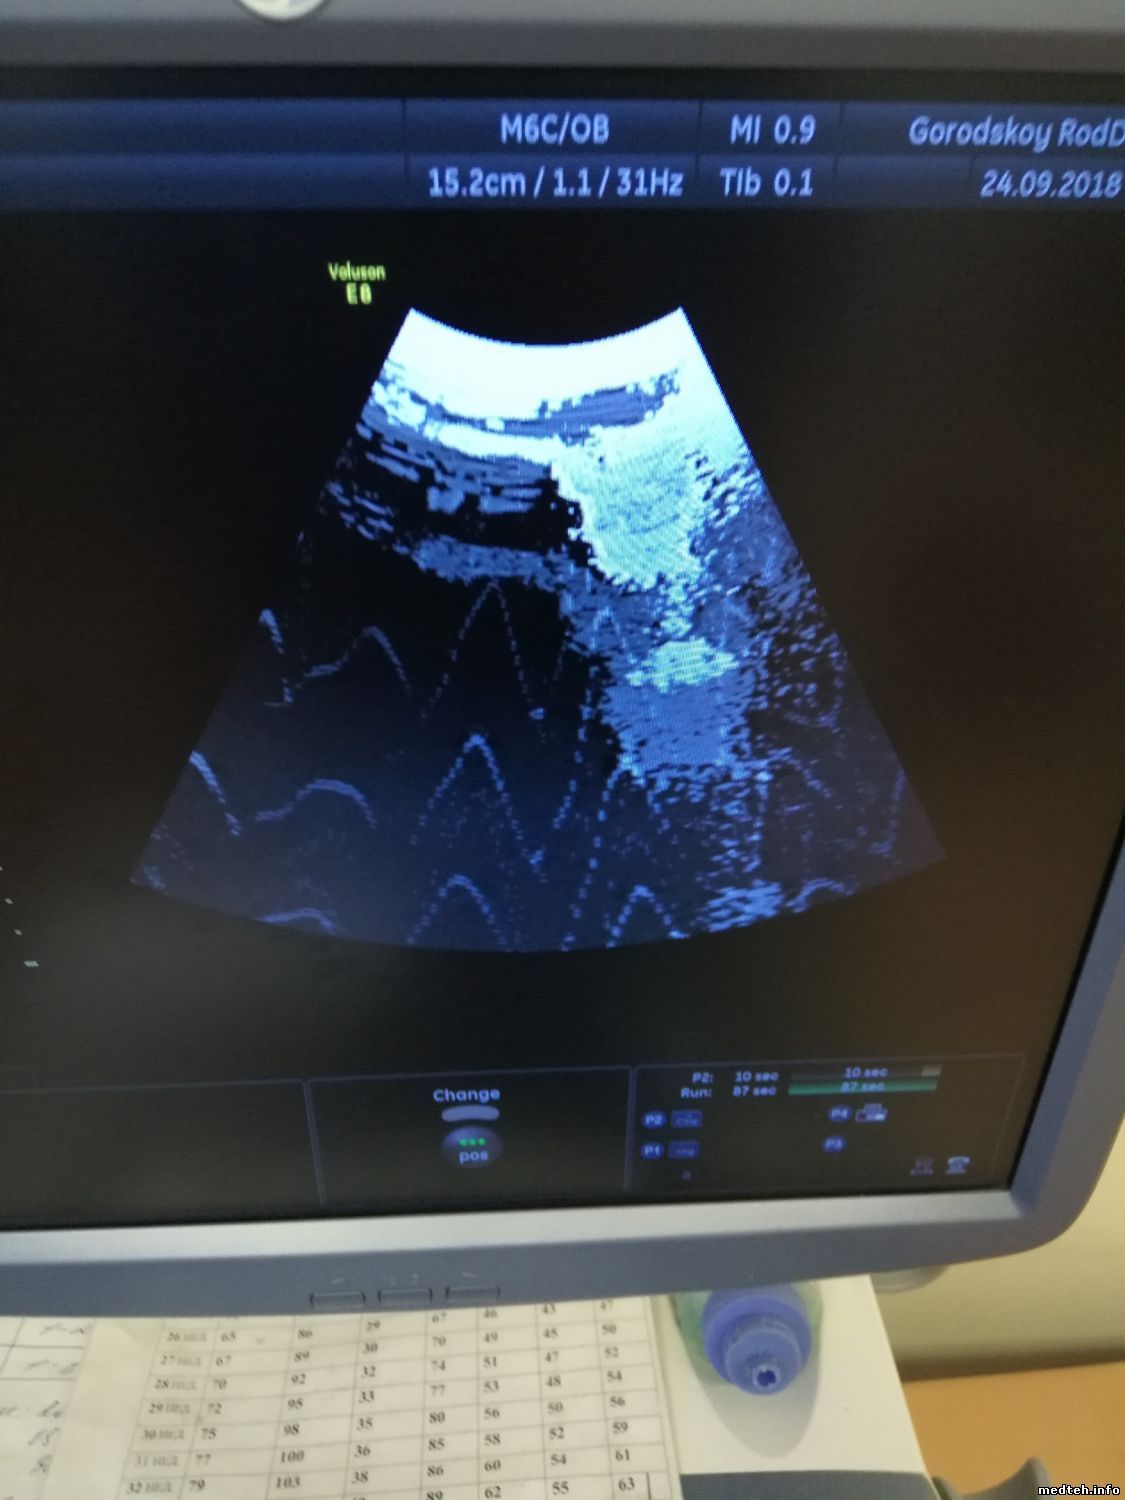

Медицинская диагностика с использованием Voluson S8 Touch